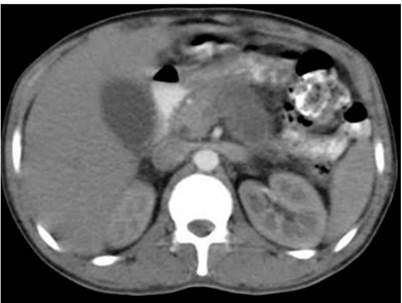

Por esta razón, el individuo consultó a la unidad de salud de II nivel de atención; allí se documentó la existencia de una hiperamilasemia de 595 mg/dL, asociada a hiperbilirrubinemia a expensas de la bilirrubina directa (Tabla 1). Además, se observaron reactantes de fase aguda positivos y hallazgos imagenológicos, mediante tomografía axial computarizada (TAC) contrastada, compatibles con pancreatitis aguda (Balthazar grado D) (Figura 1), la cual fue clasificada como moderada a severa, según el índice de severidad clínico, con un APACHE II (Acute Physiology And Chronic Health Evaluation II) de 7 puntos. En consecuencia, se indicó un manejo a partir de reanimación hídrica, cubrimiento antibiótico con ampicilina/sulbactam y suspensión de la vía oral.